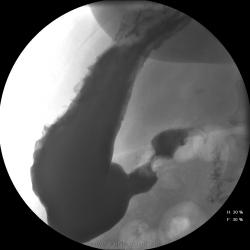

Женищина 49 лет, повышенного питания, обратилась с жалобами на потерю аппетита, жжение после чуть острой пищи, отрыжку с неприятным запахом, иногда темный стул, несколько похудела. Данные жалобы с сентебря-октября. Никуда не обращалась, коррегировала питанием. В последнее время стало хуже, обратилась...

Привратник удлиннен и ригиден, такое бывает при раке. Рек. ЭГДС.

Вы правы. я несколько недорасказал. женщина пришла уже с фгдс - инфильтративно-язвенный процесс в выходном отеде желудка у привратника по малой кривизне с переходом на переднюю стенку. так что прицельно смотрел этот отдел. перистальтка была ослаблена, краевой дефект в препилорической зоне по малой кривизне, передней стенке, кажущееся удлинение привратника, нависание основания луковицы - вообщем как в книжке. эвакуация было не изменена. написал рак выходного отдела желудка. вчера пришла гистология - высокодиф-я аденокарцинома. вот такая история.

Пока, касаясь только луковицы, но не препилорического отдела. "Ниши" в луковице есть, и они нуждаются в объяснении.

Конечно, в пилорическом канале уже растет, и "это" растет, уже и препилорической части и в луковице 12-ти перстной кишки.